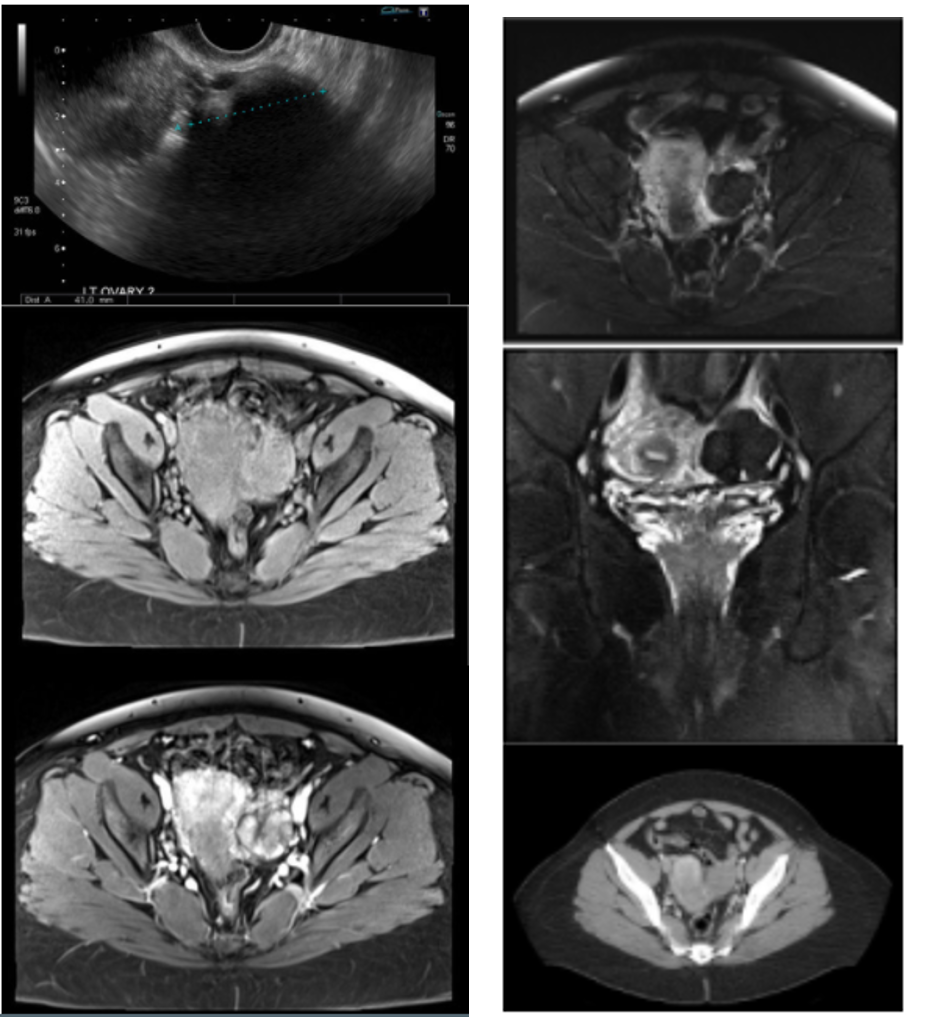

ovarian torsion

The first image demonstrates a normal right ovary. The left ovary is enlarged, midline, does not enhance normally, and demonstrates regions of restricted diffusion, compatible with ovarian torsion. The patient underwent removal of the nonviable left ovary.

most sensitive and specifics signs for ovarian torsion

sensitive sign: enlarged ovary (typically > 25mL)

Specific sign: whirpool sign (twisting of the pedicle)

Additional findings include: